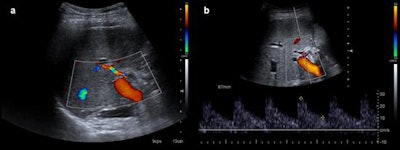

After treatment control. Control performed after thrombolysis and angioplasty of patient in previous figure. Normal arterial flow is seen. Resistive index shows normal values (0.6).Because vascular complications appear early after surgery, Doppler ultrasound should be performed by experienced staff; diagnostic angiography is seldom performed.